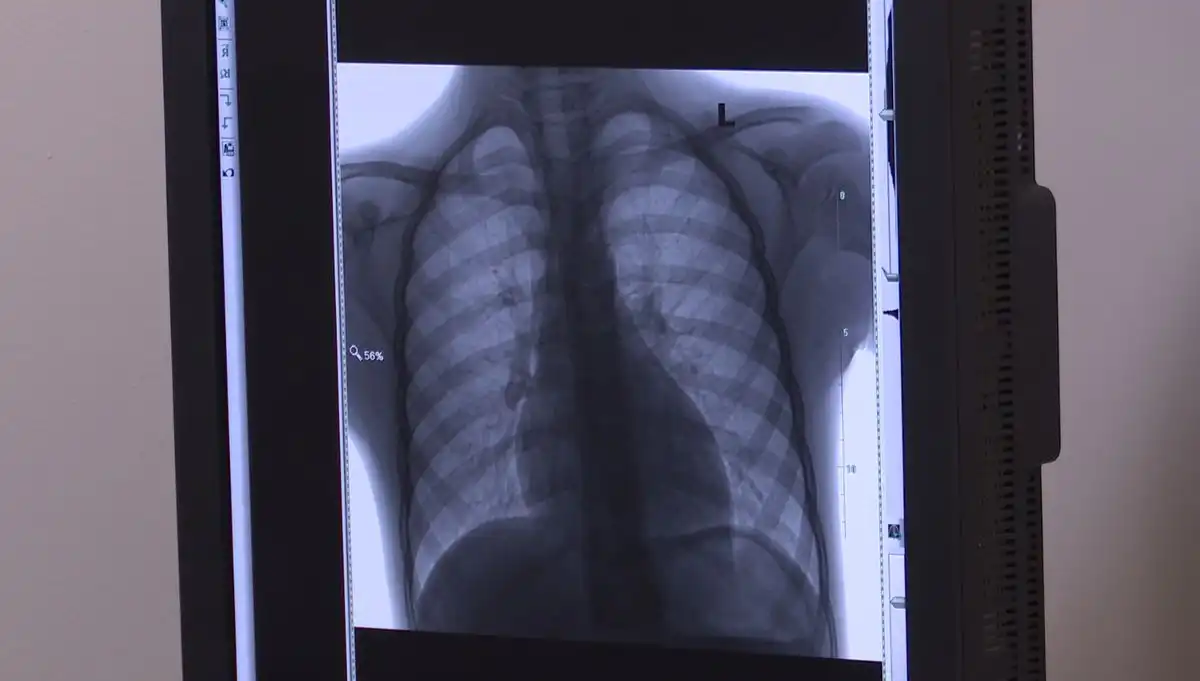

Не просто выявить туберкулёз и у взрослого населения. Его часто можно принять за простуду. Люди занимаются самолечением и запускают болезнь до сложных стадий. Именно поэтому важно проходить флюорографию не реже одного раза в год, без устали напоминают доктора.

Ежегодно работа флюоромобиля помогает выявить случаи заболевания. В эти дни выездной осмотр организован в рамках проводимой декады приуроченной ко Всемирному дню борьбы с туберкулёзом «Белая ромашка». Ее основная цель привлечь внимание к заболеванию легких и вовремя начать их лечить.